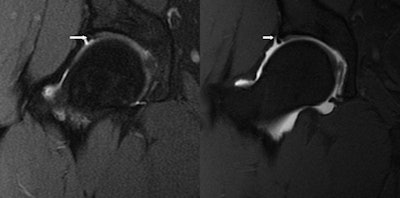

| Image shows an acetabular labral tear (arrows) via an MR image (left) and MR arthrogram (right). No additional information was needed. All images courtesy of Dr. Thomas Magee. |